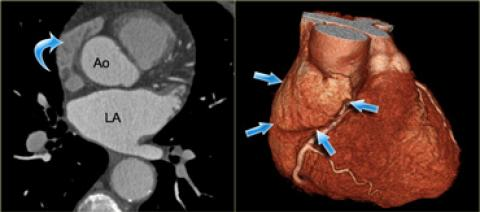

- Face postérieure du coeur

Sinus coronaire